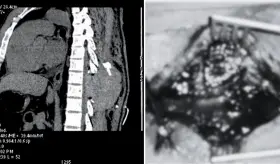

El hematoma comprimía la médula espinal y fue causado por sangrado arterial, no venoso, lo cual es poco común en estos casos.